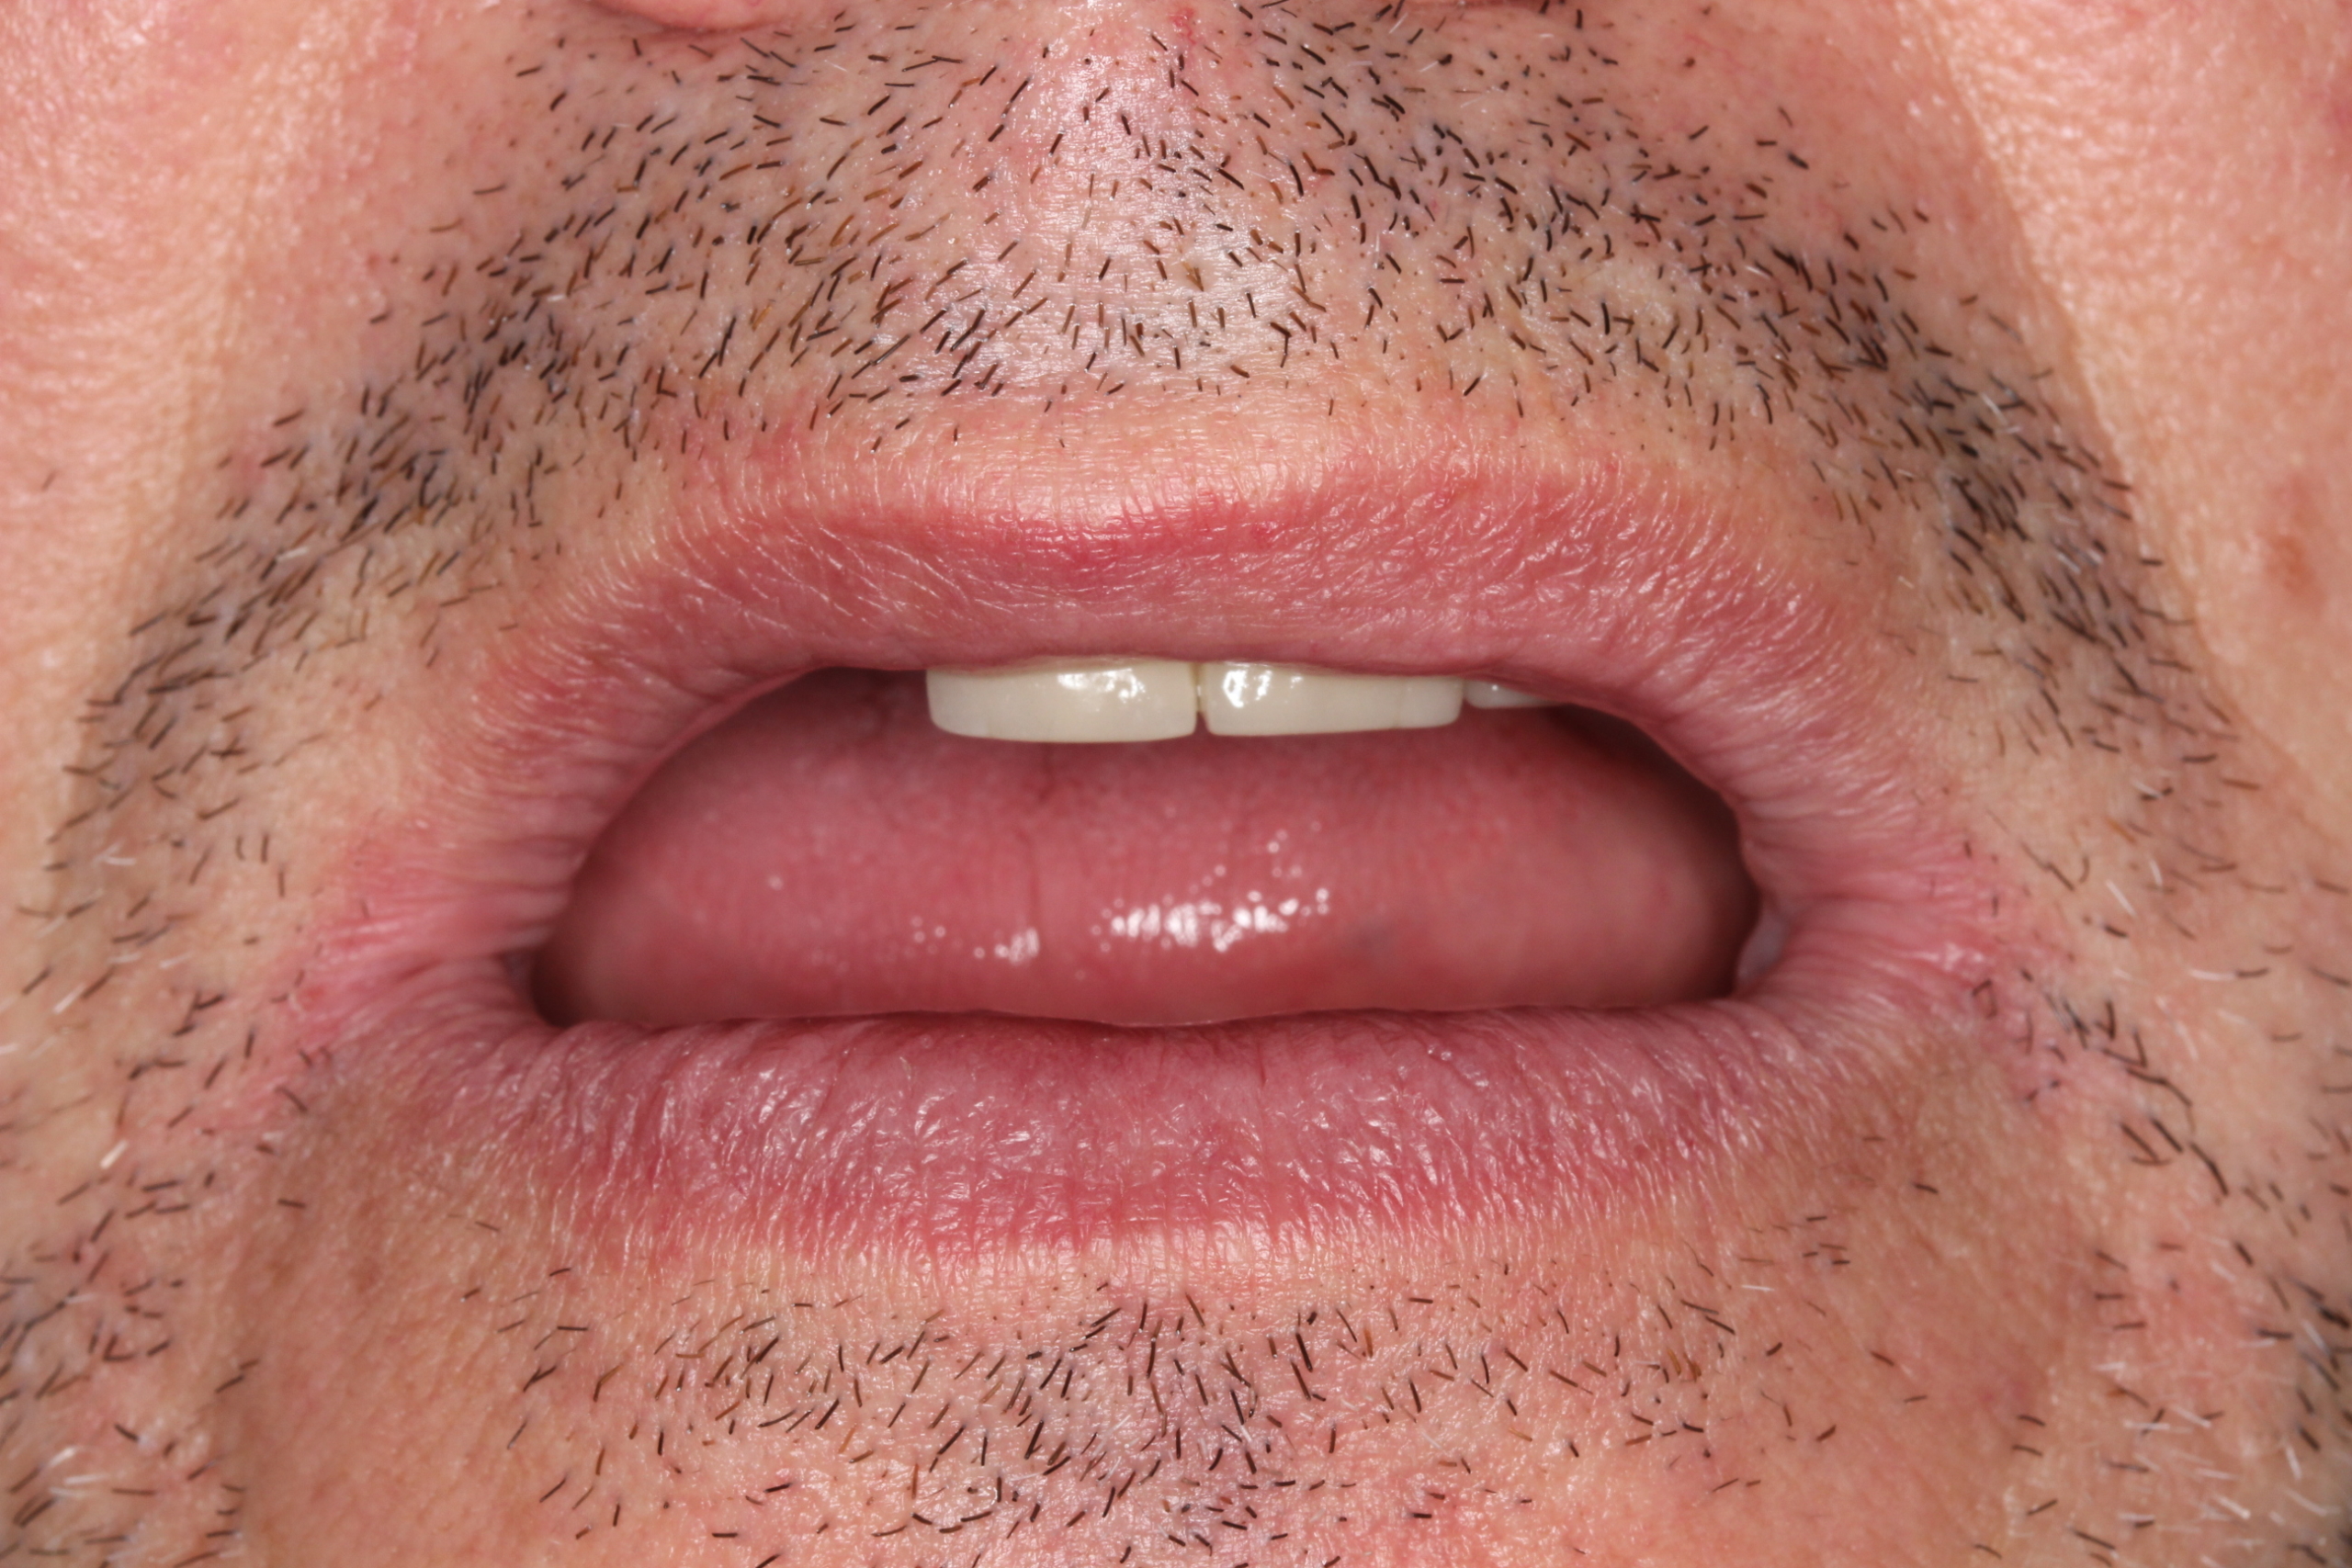

Coronas fijas en los 2 centrales.

En este caso la paciente llevaba unas coronas antiguas y se habian fracturado, se han realizado 2 coronas individuales .